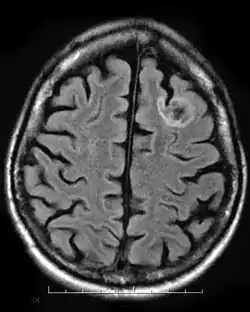

Dysembryoplastic neuroepithelial tumour (DNT, DNET) is a type of brain tumor. Most commonly found in the temporal lobe, DNTs have been classified as benign tumours.[1] These are glioneuronal tumours comprising both glial and neuron cells and often have ties to focal cortical dysplasia.[2]

A dysembryoplastic neuroepithelial tumour is commonly diagnosed in patients who are experiencing seizures with magnetic resonance imaging (MRI), electroencephalogram (EEG).[4] A DNT is most commonly diagnosed in children who are experiencing seizures, and when given medication do not respond to them. When an MRI is taken there are lesions located in the temporal parietal region of the brain.[4]